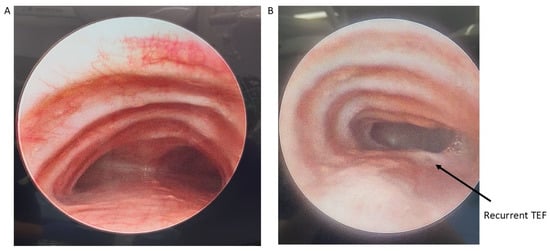

Figure 2.

Preoperative bronchoscopy demonstrating posterior tracheal intrusion in patients without (A) and with (B) recurrent TEF.

Patients with severe medically refractory cases of TM who are being considered for posterior tracheopexy should undergo thorough preoperative workup to ensure proper candidacy for this operation. Beyond the diagnosis and management of underlying associations (e.g., VACTERL in patients who previously underwent TEF/EA repair), patients should undergo “quadruple endoscopy”, incorporating laryngoscopy, dynamic bronchoscopy, distal bronchoscopy, and esophagogastroduodenoscopy (EGD) [9,13,15,19,21,29,30,31,32,33,34,35]. Laryngoscopy facilitates evaluation of the upper airway and any underlying vocal cord dysfunction that may be present preoperatively. Assessment of vocal cord function is particularly important in patients who previously underwent TEF/EA repair as they may have suffered a recurrent laryngeal nerve injury during the prior TEF/EA repair. Dynamic bronchoscopy is the gold standard in diagnosing TM and best informs the obstructive pattern present within the airway (Figure 2). Dynamic bronchoscopy is divided into 3 phases: shallow breathing, cough/Valsalva, and apneic [29]. In the first phase, patients are maintained with deep general anesthesia and allowed to spontaneously ventilate. The spontaneous ventilation phase allows for the assessment of basic airway anatomy, extraluminal compression, malformations, and secretion accumulation [36]. During the second phase, anesthesia is reduced and patients are permitted to cough, Valsalva, or otherwise vigorously breathe [29]. Observation of the airway during these increased intrathoracic pressures reveals the maximum dynamic airway collapse the patient may experience [36]. Dynamic inspection of the tracheal lumen during this period of increased intrathoracic pressure delineates the directionality of tracheal collapse and assists in the selection of an anterior or posterior surgical approach. Observation of an anterior collapse may indicate compression by an aberrant innominate trunk or otherwise aberrant anatomy, whereas posterior intrusion is more indicative of a hypermobile pars membranacea. Finally, for the apneic phase of the dynamic bronchoscopy, patients are deeply sedated again and the airways are distended to 40–60 cm H2O, which allows for identification of lesions such as TEF, tracheal diverticulum, and aberrant bronchi [36]. Distal bronchoscopy aids in the diagnosis of more distal TBM that may be less amenable to extraluminal surgical intervention. Standardized endoscopic TM scoring systems have previously been described which quantify the proximal and distal airway mobility seen during a dynamic bronchoscopy [5,6,8,13,15,17,32,33,35,37,38,39]. While these endoscopic TM scoring systems provide a useful framework for characterizing TM disease burden, they should be evaluated in conjunction with other anatomic and imaging findings to direct appropriate surgical management. Finally, EGD allows for the evaluation of possible underlying TEF, anastomotic esophageal stricture, sequela of GERD, and concomitant esophageal lesions. Ideally, all four components of a “quadruple endoscopy” are performed under a single anesthetic event to reduce morbidity for the patient and the logistical burden to families.